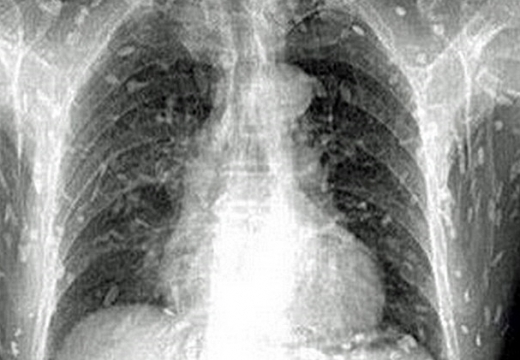

(혐오주의) 생선회 먹고 기생충이 온몸에 퍼진 남성

그냥 엑스레이사진인데 기생충이 많아요! 전 그닥 징그럽지는 않았는데 좀 소름돋긴했어요